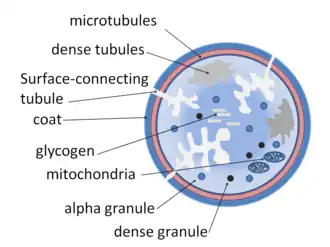

In terms of the pathophysiology of platelet storage pool deficiency one must consider several factors including the human body's normal function prior to such a deficiency, such as platelet alpha-granules one of three types of platelet secretory granule.[6]

Platelet α–granules are important in platelet activity. α–granules connect with plasma membrane. This in turn increases the size of the platelet. Platelet α–granules have an important role in hemostasis as well as thrombosis. SNARE accessory proteins control the secretion of α–granule.[6]